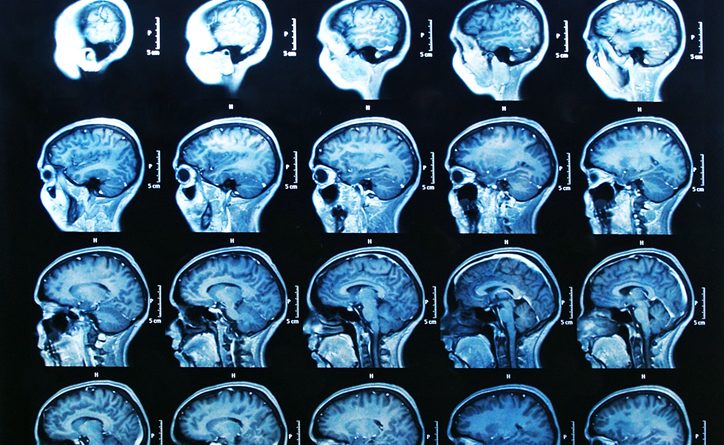

There are at least eight different types of cancer that begin in the brain. Cancer in other parts of the body may metastasize (spread) to the brain as well—often referred to as secondary brain tumors. To provide an accurate diagnosis and determine the best treatment options, healthcare professionals must also determine the stage the cancer is at. Here’s a look at how brain cancer stages are organized.

Featured Image Source: depositphotos/©Bunyos30